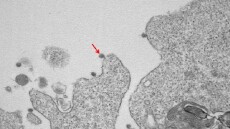

Κορωνοϊός στην Ιταλία: Ερευνητές νοσοκομείου απομόνωσαν και «φωτογράφισαν» τον ιό

Κορωνοϊός: Φωτογραφίες του ιού από κρούσματα της Λομβαρδίας, όπως αυτές τραβήχτηκαν από ηλεκτρονικό μικροσκόπιο, έδωσαν στη δημοσιότητα ερευνητές εργαστηρίου λοιμωδών νοσημάτων νοσοκομείου στο Μιλάνο